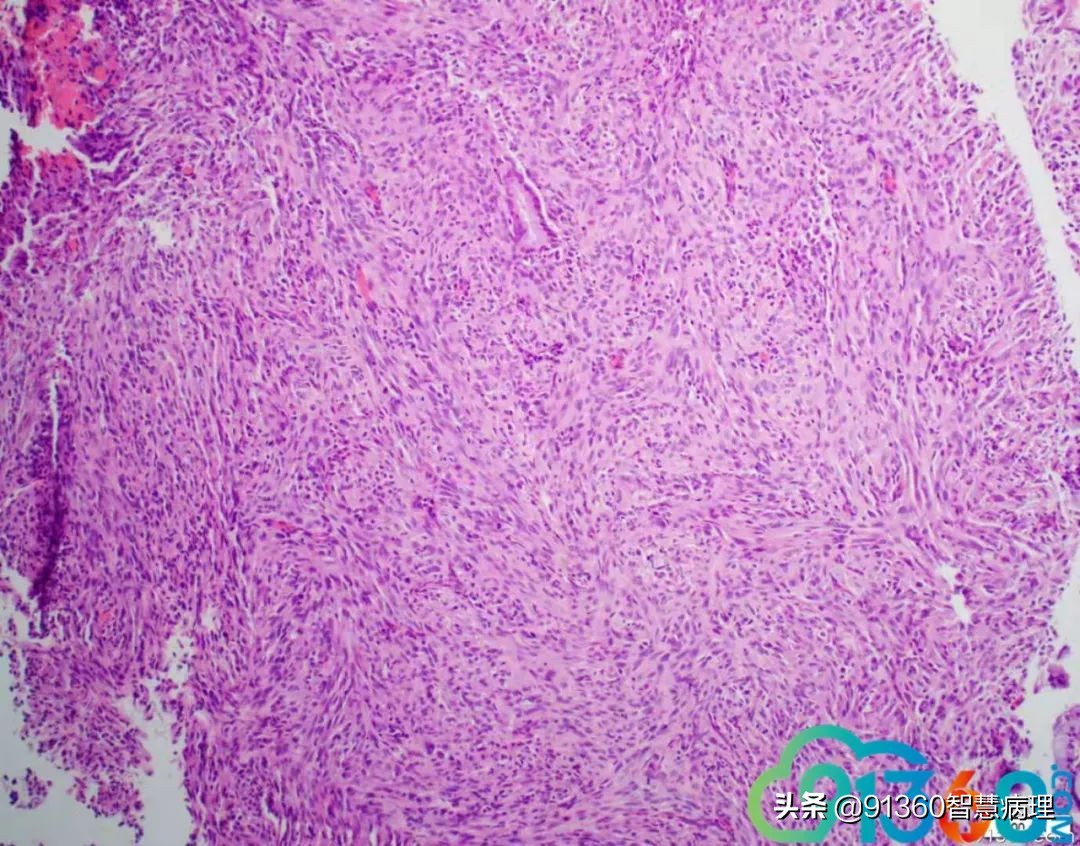

邢德印 39岁,宫颈活检 石岩 腺肉? 任永昌 梭形细胞恶性肿瘤,肉瘤首考,肉瘤样癌次之! 郭晓静 @邢德印(妇科病理)邢老师, 周末好!您的病例肯定有难度谢谢分享!抛砖引玉,我说下自己看法。1.39岁,为什么要活检?hpv情况和液基肯定有问题2.低倍这一点给我的感觉是有异型,其他很多似乎很弥漫,没有找到鳞状上皮,梭形细胞样

邢德印 Desmin -Sarcomatoid carcinoma; spindle cell carcinoma 石岩 @邢德印(妇科病理) 好例子 邢德印 以前没见过这么明显的,太肉瘤样了 任永昌 @邢德印(妇科病理) 赞 郭晓静 @邢德印(妇科病理) 我偏向猜的答案也是这个,。谢谢分享! 王昀 @邢德印(妇科病理) 好例子,没见过这么弥漫肉瘤样的,回过头来看,好像还是有点结构的样子